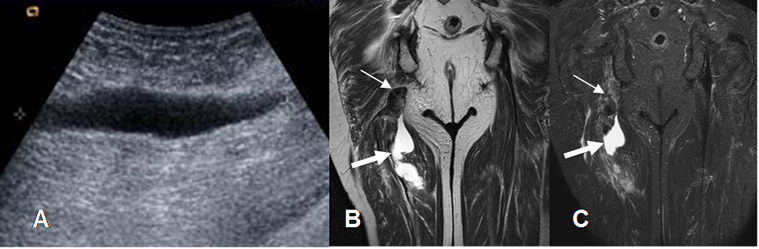

Fig 23. Ruptura muscular.

A: Ecografía longitudinal. Colección líquida, que corresponde a hematoma.

B: RM coronal en T2 y C: RM coronal en STIR. Ruptura en el origen de los isquiotibiales, con extremo retraído. (Flechas delgadas). Existe hematoma intermuscular asociado. (Flechas gruesas).